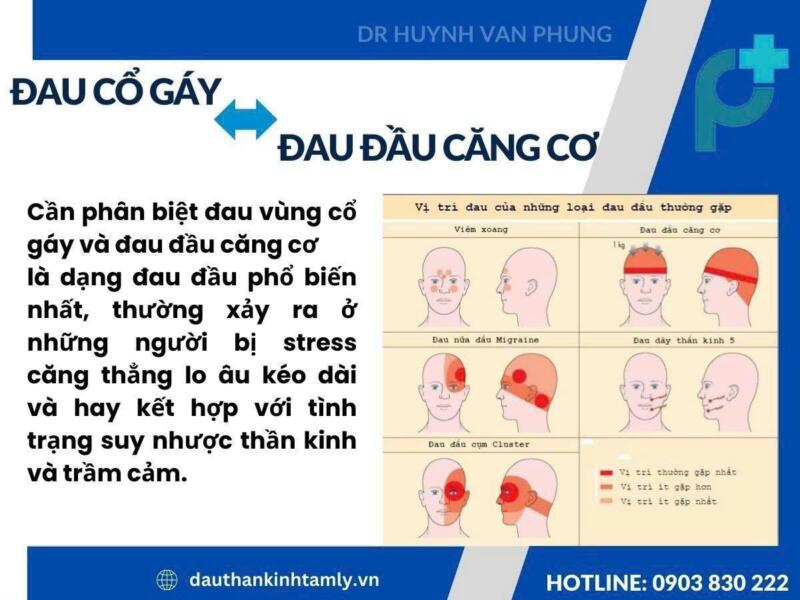

Đau đầu căng cơ và đau cổ gáy do thoái hóa cột sống cổ